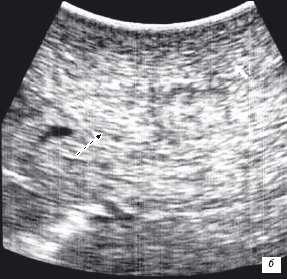

Особенностью проведения интраоперационного ультразвукового исследования у пациентов с первичным поражением печени является то, что гепатоцеллюлярный рак часто развивается на фоне цирроза печени. Следовательно, если опухоль локализуется в толще паренхимы, а так же имеет не большие размеры, пальпаторно определить ее границы крайне затруднительно. Таким образом, задачи установленные перед интраоперационной ультразвуковой томографией были несколько иными, а именно: определение границ опухоли, разметка зоны резекции, определение связи с магистральными сосудами (рис. 2 а,б).

Рис. 2. Метастатические очаги (стрелки) в печени на фоне цирроза.

Клинический пример N3. Пациент Ш. находился на лечении в ГУ РОНЦ РАМН с диагнозом гепатоцеллюлярный рак. При проведении стандартного ультразвукового исследования в правой доле печени было выявлено образование, занимающее практически всю правую долю, с четкими, неровными контурами. На операции пальпаторно определить границу опухоли и неизмененной ткани не представлялось возможным. При проведении интраоперационного ультразвукового исследования была обозначена граница опухолевого образования и неизмененной паренхимы и соотношение этого образования с сосудами печени.